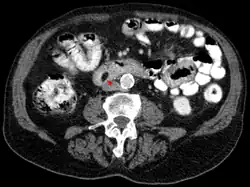

Lipom des Duodenums im CT: Den gutartigen Tumor erkennt man an den fettgleichen Dichtewerten.

Die radiologische Beurteilung ist in bis zu 71 Prozent der Fälle diagnostisch. Die Computertomographie (CT) und speziell die Magnetresonanztomographie (MRT) sind als bildgebende Verfahren in der Einschätzung des Tumors hilfreich. Im MRT sind Lipome – unabhängig von der gewählten Pulssequenz – isointens (gleiche Signalintensität) mit dem subkutanen Fettgewebe. Mit Ausnahme der um das Lipom befindlichen Kapsel erhöht sich der Kontrast bei der Gabe eines Kontrastmittels – beispielsweise Gadotersäure – nicht. In 37 bis 49 Prozent der Fälle ist im CT oder MRT ein dünnes Septum von weniger als 2 mm zu erkennen, was als nahezu pathognomonisch für die Diagnose eines Lipoms gesehen wird.[6][20] Die wesentlichen Kriterien zur Unterscheidung zwischen gutartigem Lipom und bösartigem Liposarkom sind in den meisten Fällen das Fehlen eines Septums, das Vorhandensein von mineralisierten Bereichen und die Interdigitation (eine Verzahnung benachbarter Zellen durch fingerförmige Zellfortsätze) mit der Skelettmuskulatur (Ausnahme: intramuskuläre Lipome).[6][7] Selbst erfahrene Diagnostiker können ein Lipom aber nur in 79 % der Fälle richtig von einem Liposarkom unterscheiden. Es wird daher vorgeschlagen, diese Tumoren in der Bildgebung grundsätzlich als niedriggradige Fetttumoren zu bezeichnen.[21]